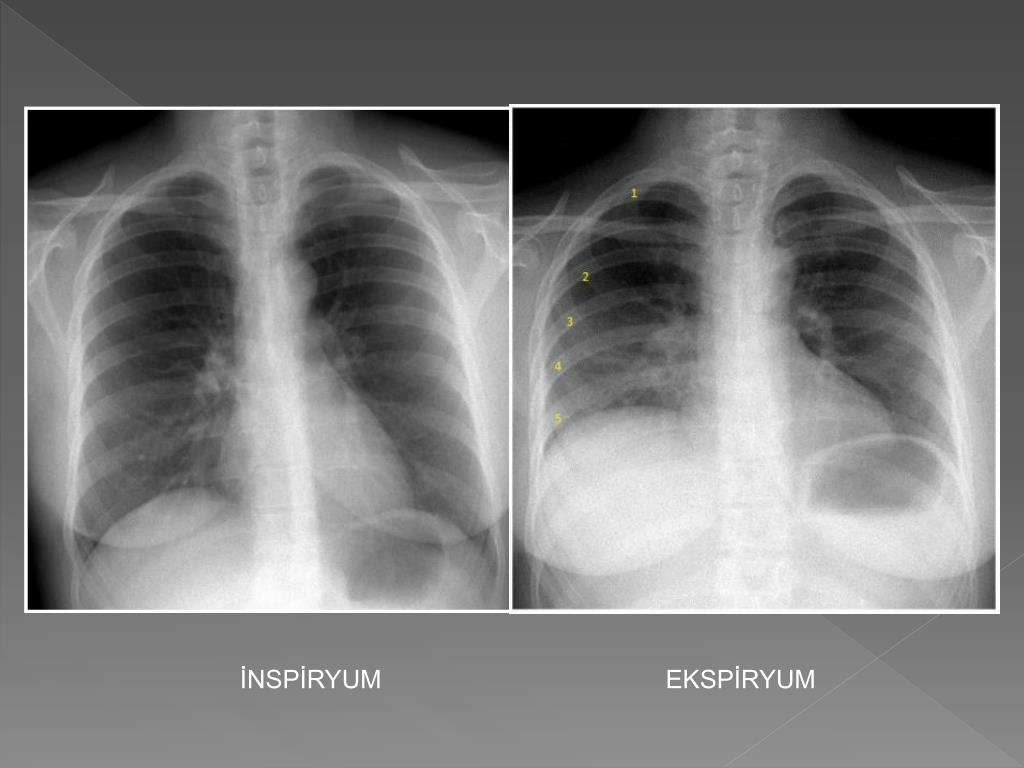

12. İNSPİRYUM EKSPİRYUM